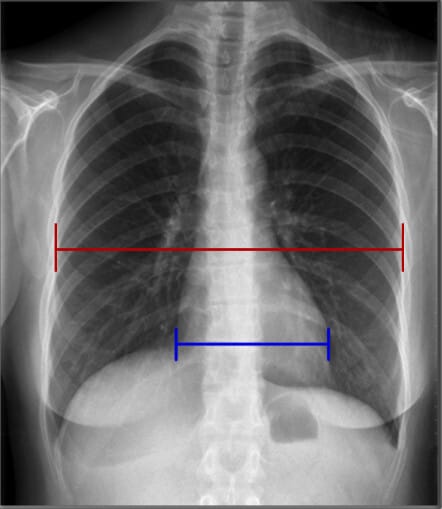

Landmarks in Chest X-ray (PA view)

폐와 심장 및 흉곽 구조물을 분석할 때 유용한 해부학적 지표로는 유방 음영(breast shadows), 심장 크기(cardio-thoracic ratio), 늑골횡격막각(costophrenic angles), 위 기포(gastric bubble) 등이 있습니다.

| 심장 크기 (Cardiac Width) |

| ✅ 정상적인 심장 크기는 흉곽 폭의 50% 이내여야 하며, 이를 심흉비(cardiothoracic ratio, CTR)라고 합니다. 비정상적으로 증가하면 심부전 또는 심장 비대의 가능성을 고려해야 합니다. |

| 늑골횡격막각 (Costophrenic Angles) |

✅ 폐 하부와 횡격막이 만나는 부분으로, 정상적으로 뚜렷하고 날카로워야 합니다. ✅ 둔해지거나 소실되면 흉수(pleural effusion) 가능성을 시사합니다. |